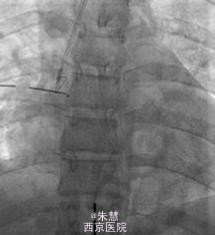

起初尝试使用支气管镜取出异物没有成功,并且还造成右侧张力性气胸,进而给予胸腔闭式引流进行治疗。由于订书钉经常从血管钳上滑落,采用微型捕捞器将其固定在支气管导管的远端。之后将支气管导管、引导导管、捕捞器、订书钉一起取出,取出的过程中,订书钉的尖端朝里,以防止声带被异物损伤。透视介导的时间长度一共是22分钟。患者术后未出现并发症,并于第二天出院。